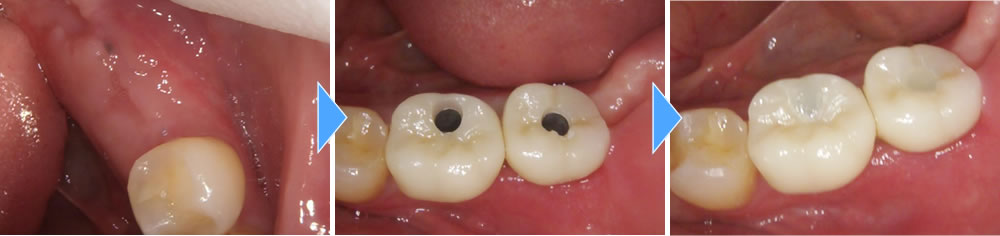

大臼歯2本分欠損していたため、しっかりと噛み合うよう、インプラントも2本埋入しました。

埋入したインプラントと顎骨がしっかりと結合した後、上部構造を製作・装着して治療完了となりました。治療後は、もともとあった歯と同じように違和感なく噛めるようになり、大変満足していただいております。